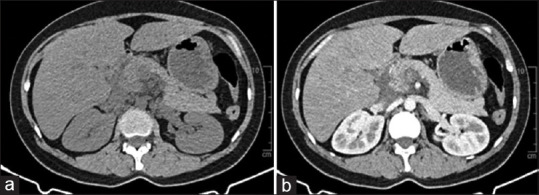

Acute pancreatitis is one of the severe complications of hypertriglyceridemia, which needs to be recognized early to provide appropriate treatment. Hypertriglyceridemia-induced pancreatitis has several causes, in which in vitro fertilization (IVF) is a rare etiology that is becoming increasingly popular. We report a 33-year-old female patient with a history of hypertension who has failed an IVF cycle and started a new IVF procedure 1 month before admission. She was diagnosed with severe triglyceridemia-induced acute pancreatitis with extremely high serum triglycerides (TGs) levels (18,547 mg/dL). We combined plasmapheresis and intravenous (IV) insulin and significantly reduced blood TG over a short time. She was discharged with a TG level of 366.7 mg/dL on the 10th day. It is essential to monitor serum TG levels in plasma before, during, and after this therapy, especially in the 1st month after initiating IVF. Although plasmapheresis combined with IV insulin is not officially recommended for acute triglyceridemia-induced pancreatitis, the therapy can be considered in cases with extremely high serum TG levels.